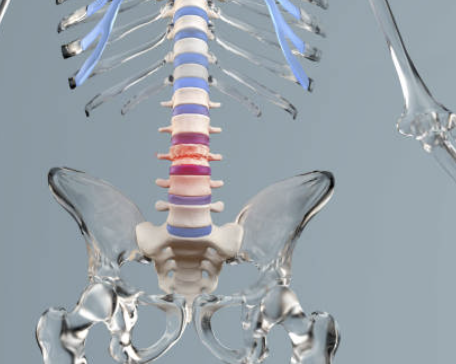

1. 허리 협착증이란?

허리 협착증은 척추관이 좁아져 신경을 압박하면서 통증을 유발하는 질환이에요. 주로 나이가 들면서 발생하는 퇴행성 질환으로, 허리와 다리에서 통증이 나타날 수 있어요. 특히 오래 걸으면 다리가 저리고, 앉거나 쭈그려 앉으면 증상이 완화되는 것이 특징입니다.